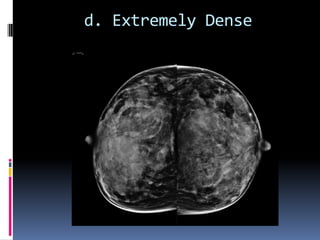

 d.The breasts are extremely dense, which lowers the

sensitivity of mammography

d. Extremely Dense